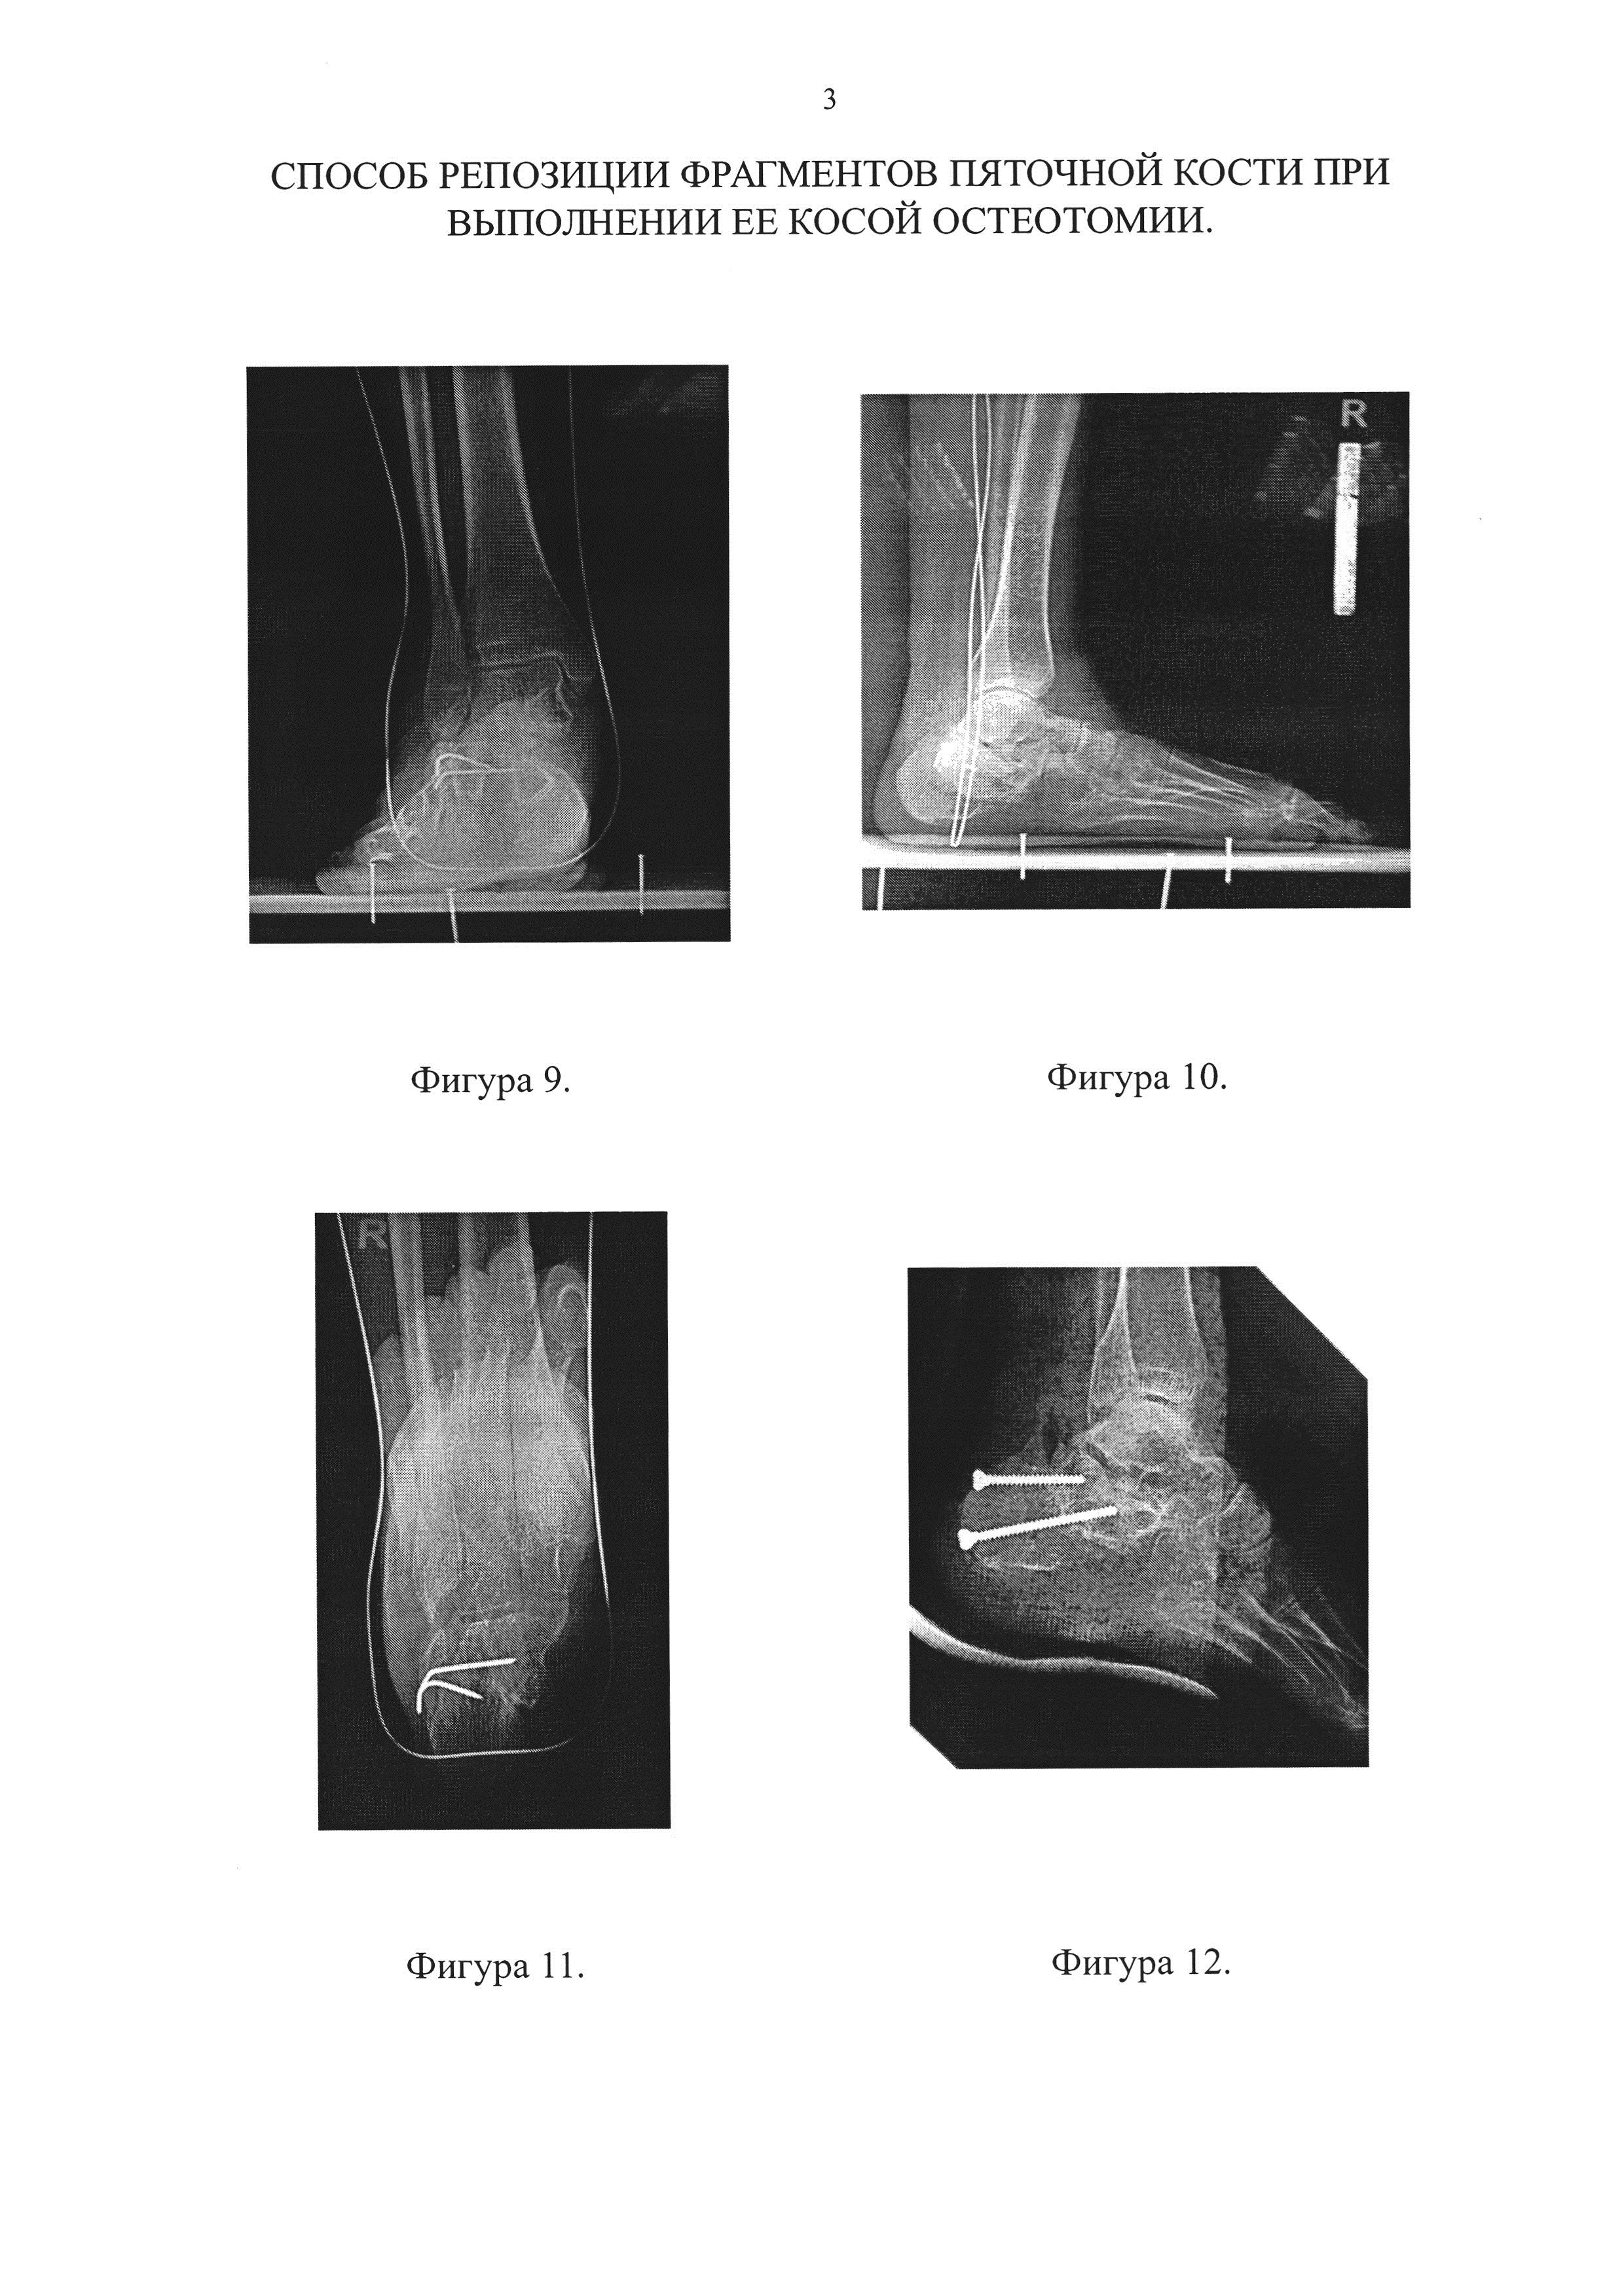

Фигура 9. Рентгенограмма правого голеностопного сустава пациентки в прямой проекции до оперативного лечения.

Фигура 10. Рентгенограмма правой стопы пациентки в боковой проекции до оперативного лечения.

Фигура 11. Рентгенограмма правой пяточной кости в аксиальной проекции до оперативного лечения.

Фигура 12. Рентгенограмма правой стопы пациентки в боковой проекции в первые сутки после выполненной операции.

В ходе операции выполнили остеотомию правой пяточной кости с последующей репозицией заднего фрагмента пяточной кости по предложенной нами методике и металлоостеосинтез двумя винтами (Фиг. 12, 13).

Послеоперационный период протекал без осложнений. Через три месяца после операции по результатам контрольного осмотра, рентгенографии и компьютерной томографии было отмечено сращение в области остеотомии пяточной кости с восстановлением анатомии пяточной кости (Фиг. 14-16).